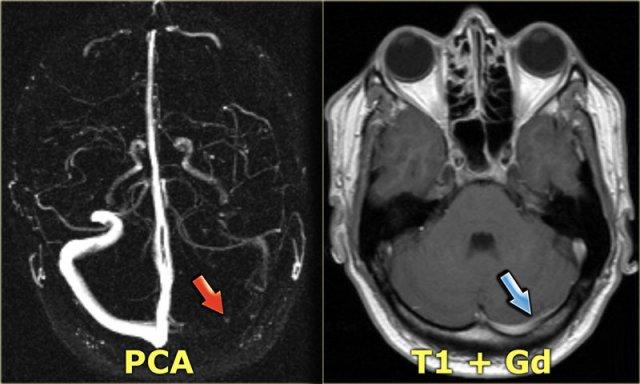

Chụp tĩnh mạch MR (MR-venography)

Các kỹ thuật MRI được sử dụng để chẩn đoán huyết khối tĩnh mạch não bao gồm:

Chụp mạch thời gian bay (Time-of-flight – TOF), chụp mạch tương phản pha (Phase-contrast angiography – PCA) và chụp tĩnh mạch MR có tiêm thuốc tương phản từ:

Chụp mạch thời gian bay (TOF) dựa trên hiện tượng tăng tín hiệu liên quan đến dòng chảy của các spin đi vào lớp cắt.

Do chưa bị bão hòa, các spin này tạo ra tín hiệu mạnh hơn so với các spin xung quanh đã bị bão hòa. - Chụp mạch tương phản pha (PCA) sử dụng nguyên lý rằng các spin trong máu di chuyển cùng chiều với gradient từ trường sẽ tạo ra độ lệch pha tỷ lệ thuận với vận tốc của các spin.

Thông tin này có thể được dùng để xác định vận tốc của các spin. Hình ảnh này có thể được trừ đi từ hình ảnh thu được mà không có gradient mã hóa vận tốc để tạo ra hình ảnh mạch máu. - Chụp tĩnh mạch MR có tiêm thuốc tương phản từ sử dụng hiệu ứng rút ngắn thời gian T1 của Gadolinium.

Kỹ thuật này tương tự như chụp tĩnh mạch cản quang CT.

Khi sử dụng hình ảnh tái tạo MIP, luôn luôn phải xem xét các hình ảnh gốc (source images).

Bên trái là hình ảnh MIP theo mặt phẳng đứng dọc và chếch của một ca chụp tĩnh mạch MR có tiêm thuốc tương phản từ bình thường.

Lưu ý tĩnh mạch Trolard nổi bật (mũi tên đỏ) và tĩnh mạch Labbe (mũi tên xanh lam).

Mỗi kỹ thuật MRI đều có những bẫy chẩn đoán riêng mà chúng ta sẽ thảo luận sau.

Chụp tĩnh mạch MR có tiêm thuốc tương phản từ có nhược điểm là cần tiêm thuốc, nhưng có ít bẫy chẩn đoán hơn.